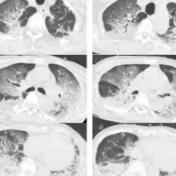

入院时,韩爷爷意识不清,血压、心率下降,医生随即为他安排头颅、胸部CT和肺血管CTA检查,结果显示,老人的双肺出现大面积白色影像。经会诊,韩爷爷被确诊为热射病诱发的肺水肿。